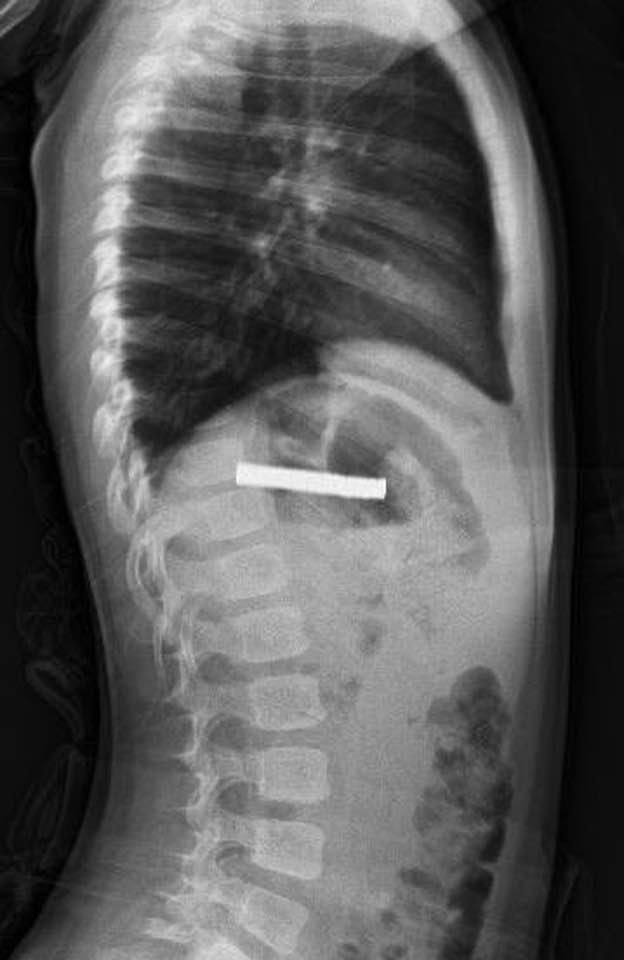

Elazığ’da 3 yaşındaki bir çocuğun yuttuğu 19 mıknatıs, Fırat Üniversitesi Hastanesinde başarılı bir operasyon ile çıkartıldı.

Edinilen bilgiye göre, Erzurum’da bir çocuk evde bulunan 19 tane mıknatısı yuttu. Çocuğun rahatsızlanması sonucu durumu öğrenen aile hastaneye başvurdu. Daha sonra çocuk Elazığ’a sevk edildi. Fırat Üniversitesi Çocuk Gastroenteroloji Hepatoloji ve Beslenme Bilim Dalı Başkanı Prof. Dr. Yaşar Doğan, çocuk hastanın yemek borusuna yapışmış 19 mıknatısı endoskopik yöntemle çıkardı.

Mıknatıslar uzun süre yemek borusunda takılı kaldığı için yemek borusu ve mide girişinde zedelenmeler olurken, çocuğun sağlık durumunun iyi olduğu ve taburcu edildiği öğrenildi.

Çocuğun boğazından 19 adet mıknatıs çıkartıldı